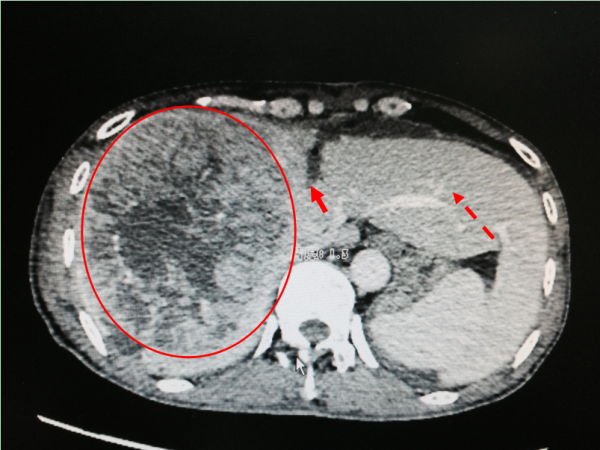

手术前CT图:红圈为肝肿瘤

ALPPS第一步(门静脉结扎及左右半肝的离断)手术后CT图:红圈为肝肿瘤;实心箭头为左右半肝离断处;虚线箭头为增生左肝叶。